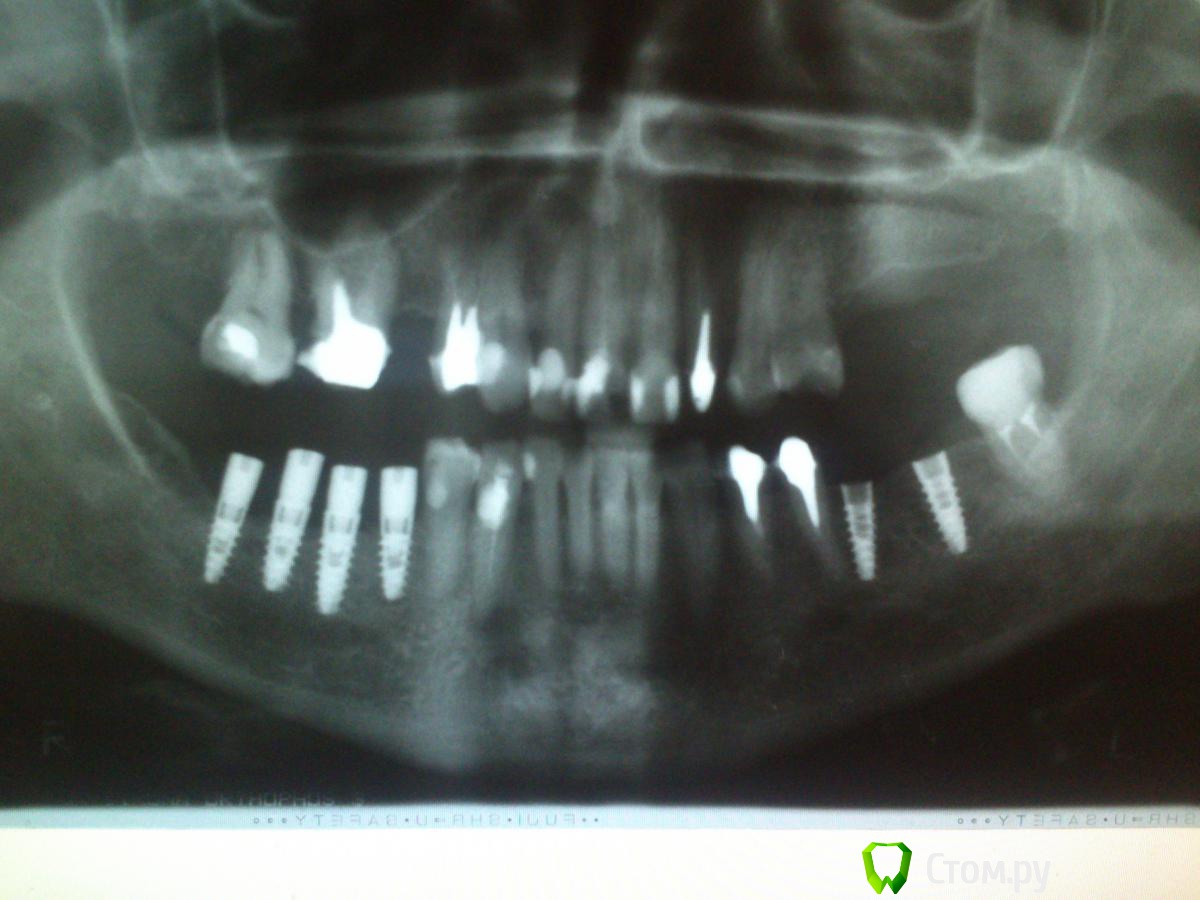

GoDemon Опубликовано 30 сентября, 2014 Поделиться Опубликовано 30 сентября, 2014 Здравствуйте, коллеги. Ситуация такая, пациентке ставил импланты пол года назад, альвеолярный отросток визуально узкий, не был уверен, что вообще получится хоть что-то туда установить. Когда раскрылся, оказалось, что места не разгуляешься , но хватает . Поставил тогда четыре импланта , мис - севен: 3,75-10, 4,2-11,5, 4,2-10, 3,75-10 . На следующий день все ок, а дальше сложности. Когда пришла снимать швы, в области двух центральных винтов видны заглушки. Я деэпителизировал края, ушился заново, основательно, в два слоя, и все равно, когда надо было швы снимать, заглушка одного импланта была видна... Оставил так, и она затянулась ( я уже значительно позже прочитал на форуме , что нужно было фдм-ки ставить... Ну да ладно... Пациентку вообще протезировать не я должен был, подготовка к протезированию не мной проводилась, вкладки тоже не мои... Но вскоре ее отправили, сказали, что слева тоже зубы не надежные, мосты ставить на них нельзя, пусть доктор ставит импланты и протезирует, раз уже начал... Слева гребень был шире, но когда раскрылся , оказалось, что вестибулярно в позиции 3.6 отсутствует кортикалка, а в самой лунке что-то типа фиброзной ткани... Я попытался кость восстановить, и, к моему удивлению, получилось. Через четыре месяца после аугментации поставил там два импланта, но на снимке увидел атрофию в области имплантов справа... Огорчение на целый день, блин... Сам думаю, что близко друг к другу поставил, может заглушка прорезовшаяся повлияла, или, может, все же гребень узковат был( правда все импланы были костью окружены достаточно, как мне казалось) ... Подскажите пожалуйста, в чем, на ваш взгляд, главная причина и что теперь делать , можно ли на них протезировать, или надо убирать? Стоят они неподвижно, Имплантов самих не видать, фдм -ы в десну погружены... Спасибо всем, кто осилит столько букв, и даст совет) И , традиционно, прошу прощение за качество приложенных рентгенограмм) Ссылка на комментарий

syrovovec Опубликовано 30 сентября, 2014 Поделиться Опубликовано 30 сентября, 2014 Да, в четвертом секторе титана перебор, почти как по параскевичу, количество корней минус 1 = кол-во имплантов)Но мне кажется убирать ненужно, если с десной порядок 2 Ссылка на комментарий

Bier Опубликовано 1 октября, 2014 Поделиться Опубликовано 1 октября, 2014 в 4м сегменте надо было 2 имплантата ставить вместо 4х 5 Ссылка на комментарий

faity Опубликовано 1 октября, 2014 Поделиться Опубликовано 1 октября, 2014 А зачем вы в области 4.8 заимплантировались? 4 Ссылка на комментарий

GoDemon Опубликовано 1 октября, 2014 Автор Поделиться Опубликовано 1 октября, 2014 А зачем вы в области 4.8 заимплантировались?При смыкании зубов 1.7 не в прикусе получался бы. Я последний имплант вообще не планировал ставить, по неопытности заметил, что семерка из прикуса выпадает только когда три поставил и попросил зубы сомкнуть... Такой вот косяк в планировании... Пришлось еще один доставлять... Ссылка на комментарий